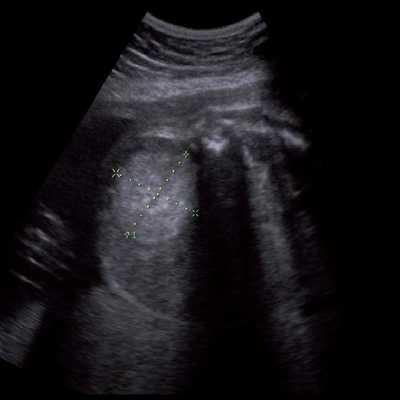

Под диафрагмой справа визуализировалось гиперэхогенное опухолевидное образование несколько неоднородной солидной структуры, с четкими ровными контурами, размером 50x38x35 мм. К нижнему полюсу данного образования прилежала правая почка, имеющая нормальные размеры, форму и структуру. Нижняя полая вена была смещена кпереди и влево. Обращала на себя внимание выраженная гепатомегалия, причем структура печени не была однородной. Она содержала множественные гиперэхогенные включения размерами до 17 мм, окруженные тонким гипоэхогенным периферическим ободком. Цветовое допплеровское картирование(ЦДК) демонстрировало интенсивную периферическую васкуляризацию опухоли (рис. 1-3).

Рис. 1. Нейробластома правого надпочечника плода. Беременность 31 нед 4 дня.

В представленном наблюдении картина нейробластомы надпочечника была не совсем классической. То, что это супраренальное образование - очевидно, так как оно прилежало к почке, имеющей нормальную форму, размеры и структуру. Опухоль имела капсулу, однородную гиперэхогенную структуру, что не характерно для нейробластомы надпочечника. Поэтому дифференциальную диагностику проводили с кровоизлиянием в надпочечники, опухолью Вильмса, экстралобарным легочным секвестром, ретроперитонеальной тератомой.

Кровоизлияние в надпочечники, как правило, выглядит эхогенным или неоднородной структуры образованием, иногда может быть полностью анэхогенным и характеризуется изменением ультразвуковой картины при динамическом исследовании, постепенно превращаясь в анэхогенное кистозное образование, в котором с течением времени отмечается утолщение его стенки [13] и образуются кальцификаты. Энергетический допплер демонстрирует полную аваскулярность такого образования. В нашем случае образование имело повышенную эхогенность, несколько неоднородную структуру. При ЦДК в опухоли регистрировался преимущественно периферический кровоток.